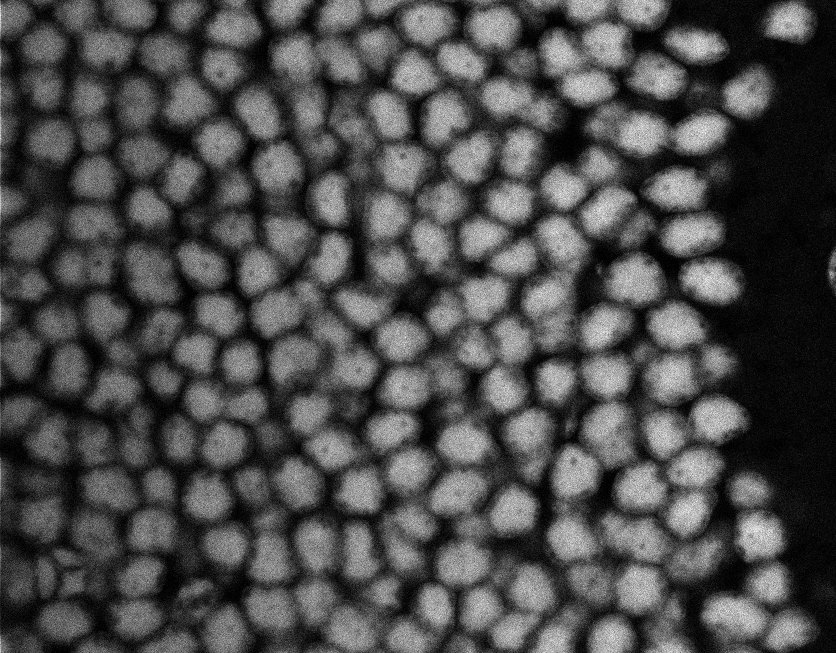

Nuclei

Nuclei - Bis

Nuclei - Bip

Nuclei - Bipolar